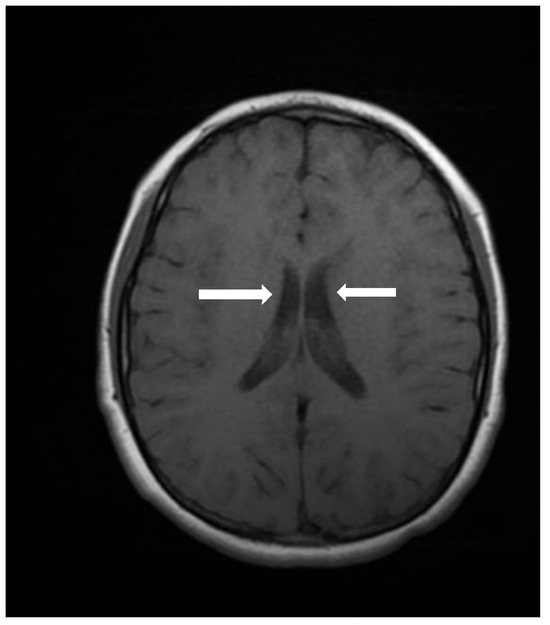

Cranial computed tomography showed a deviated nasal septum with a rightward convexity. Brain magnetic resonance imaging (MRI) with contrast revealed bilateral subependymal periventricular nodular heterotopia (PVNH) at the level of the temporal horns, with no post-contrast enhancement (Figure 3). Additionally, a right choroid plexus cyst was observed in the temporal horn. Audiometry revealed normal bilateral hearing. Neurological examinations showed only mild immaturity in fine motor coordination.

Figure 3.

An axial image of the MRI of the skull showing PVNH in both lateral ventricles. Figure legend: white arrows indicate areas of PVNH, visible as discrete ripples of gray matter adjacent to lateral ventricles.

PVNH, defined as a malformation of cortical development caused by the failure of neurons to migrate to the cerebral cortex, resulting in heterotopic nodules adjacent to the lateral ventricles, is a hallmark feature of MAP1B-related syndromes [20]. LoF variants in MAP1B are also associated with other neurodevelopmental anomalies, such as reduced white matter volume and corpus callosum [2]. However, individuals with MAP1B LoF variants exhibit a wide range of phenotypic variability, with some cases showing normal intelligence and the absence of neurological symptoms [3]. Despite this variability, PVNH appears to be the most consistent neuroanatomical finding [1,2,3].